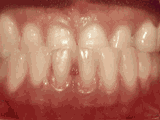

deep overbite

Deep overbite: Lower front teeth bite into palate

This adult patient (age twenty-five) required braces and jaw surgery to correct his severe overbite, with treatment taking two years. His problem could have been corrected without surgery if he had been treated before he was a teenager.